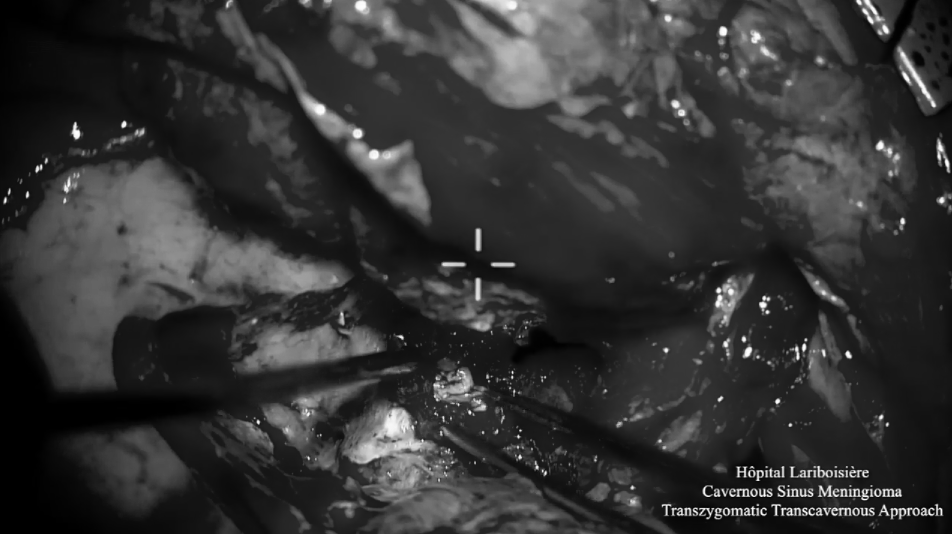

▼神经内镜下切除肿瘤后的术野

▼术腔使用自体脂肪填充

完成肿瘤切除后,闭合蝶窦。术后恢复好,无新发神经功能障碍,V2-视神经功能没有恶化。术后组织病理学为I级脑膜瘤,Ki-67指数为10%。结合患者术前肿瘤生长迅速,患者在术后3个月接受了放射外科手术。患者在放疗后16个月没有进展迹象。